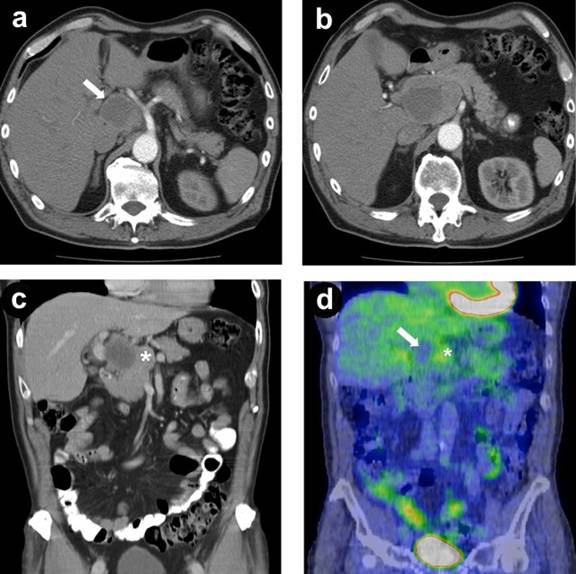

A 66-year-old man who presented with sudden onset abdominal pain, found on computed tomography (CT) to have a complex solid and cystic mass involving the head and uncinate process of the pancreas, measuring 6 cm (Figure 1). Positron emission tomography (PET) showed mild metabolical activity adjacent to the cystic component but was non-diagnostic for malignancy. Carcinoembryonic antigen (CEA) and carbohydrate antigen 19-9 (CA 19-9) were not elevated. Chromogranin A was mildly elevated at 78 U/L (reference range: 0-21.8 U/L).

Figure 1. a. Arterial phase computed tomography showing in axial image a partially cystic pancreatic head mass (arrow) with celiac artery running adjacent to it. b. The mass extended into the uncinate process of the pancreas adjacent to the superior mesenteric artery. c. The mass seen on coronal reconstruction in porto-venous phase demonstrating cystic and solid (asterisk) components. d. Computer tomography positron emission tomography (CT-PET) showing no uptake within the cystic component (arrow) of the mass with mild increased uptake in the adjacent solid component (asterisk). |